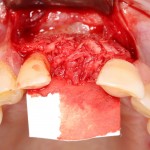

Ну и, швы: